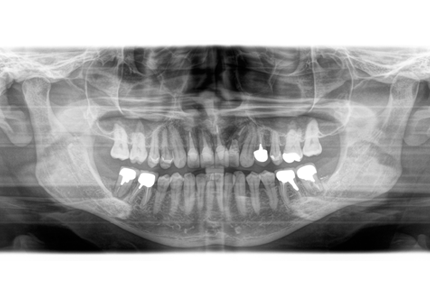

受傷時パノラマレントゲン(2018年5月17日)

【受傷時 パノラマレントゲン】

【最終補綴物装着 パノラマレントゲン】

↑ 初診時パノラマレントゲン(2023年4月1日)

↑ 右下6番最終補綴物セット時パノラマレントゲン(2025年4月22日)